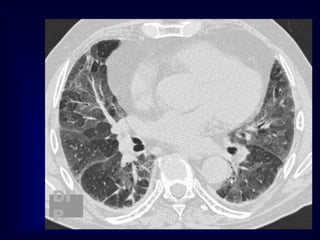

Extr. Allerg. Alveolitis (EAA)HRCT

Morphology

chronic: fibrosis

Intra- / interlobular septal thickening

Irregular interfaces

Traction bronchiectasis

acute - subacute

acinar (centrilobular) unsharp densities

ground glass (patchy - diffuse)